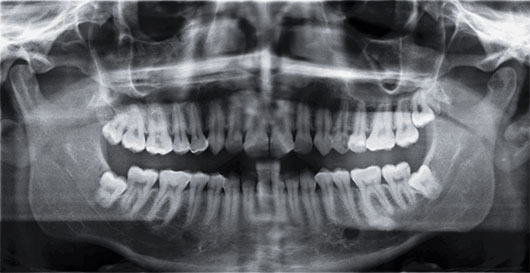

7. 아래 사진의 경우 사랑니가 신경관과 가까이 있어 신경손상의 위험이 높아 주의하여 발치해야 합니다.

1. 사랑니는 세번째 어금니를 말하며 위아래 좌우 하나씩 최대 4개까지 날 수 있으나 나지 않는 경우도 있습니다.

2. 턱뼈의 공간이 부족한 경우 대부분 기울어져 나거나 잇몸 속에 묻혀 있습니다.